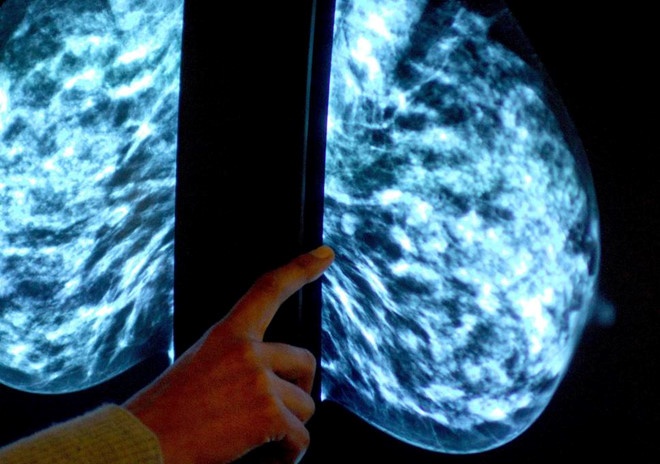

| Bệnh nhân ung thư vú nếu phát hiện sớm ở giai đoạn I, tỷ lệ sống trên 5 năm là 100%. Ảnh: Independent. |

Với bệnh ung thư nếu được phát hiện sớm, tỷ lệ sống trên 5 năm tương đối cao. Bệnh nhân ung thư vú nếu phát hiện sớm ở giai đoạn I, tỷ lệ sống trên 5 năm là 100%.